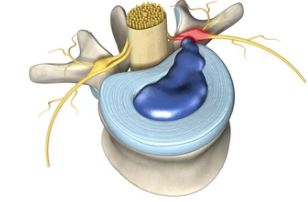

Effectiveness and Safety of Low-Level Laser Treatment for Lumbar Disc Herniation: A Systematic Review and Meta-Analysis Sang Jun Lee1, Seung Jin Noh2,3, Jeong Rock Kim2, Kyung Bok Park2, Sae-rom Jeon2, Yejin Hong2, Dongwoo Nam2,3,* Perspectives on Integrative Medicine 2023;2(3):155-163. DOI: https://doi.org/10.56986/pim.2023.10.003

J Healthc Eng. 2022; 2022: 6437523. Published online 2022 Feb 27. doi: 10.1155/2022/6437523 PMCID: PMC8898844 PMID: 35265302 Effectiveness of Low-Level Laser Therapy in Patients with Discogenic Lumbar Radiculopathy: A Double-Blind Randomized Controlled Trial Ishaq Ahmed, 1 Mohammad Ali Mohseni Bandpei, 2 Syed